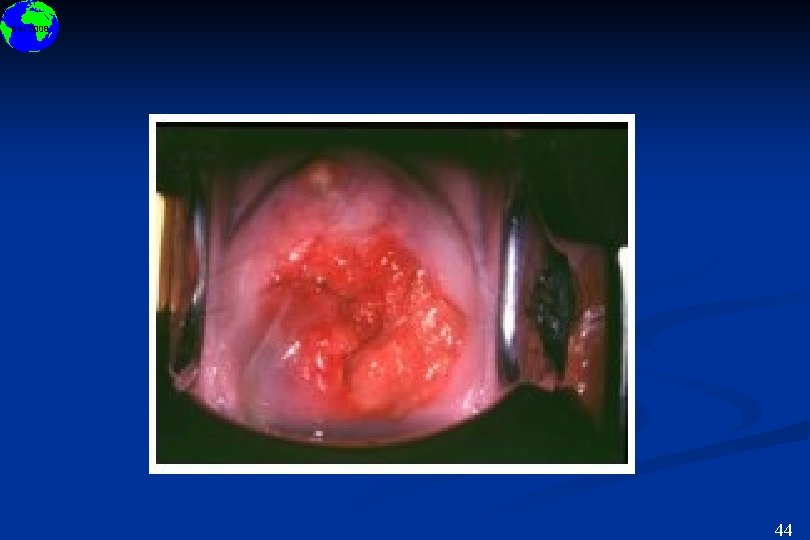

DIU 2008 Localisations muqueuses - Fréquence < - Muqueuses oculaire, buccales et génitales 6

DIU 2008 44